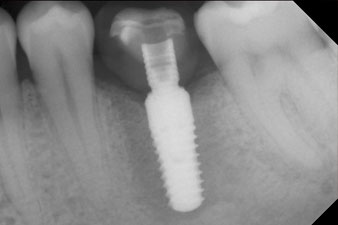

x-ray check

Fig. 10: The x-ray check shows the success of the osseointegration and the crown screwed in position without a gap.

The final pictures show the screw-retained monolithic composite crown in place and the x-ray check (Fig. 9 and 10) (6).